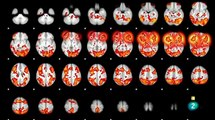

Sumérgete en un viaje fascinante a través de la psique criminal con el documental "En la mente del asesino". Descubre los intrincados pensamientos y motivaciones que impulsan a individuos a cometer actos atroces, explorando casos reales que han impactado a la sociedad. Acompáñanos en esta investigación educativa que analiza de cerca el comportamiento humano más oscuro y perturbador, ofreciendo una visión única sobre la mente criminal. Desde perfiles psicológicos hasta testimonios expertos, este documental te llevará a un nivel más profundo de comprensión sobre la naturaleza del mal. <br /><br />Los hashtags más relevantes para este tema son: #MenteDelAsesino, #PsicologíaCriminal, #DocumentalCriminología. <br /><br /> Mente del Asesino, Psicología Criminal, Documental, Comportamiento Criminal, Casos Reales, Perfiles Psicológicos, Naturaleza del Mal, Investigación Criminal, Motivaciones Asesinas, Análisis Forense.